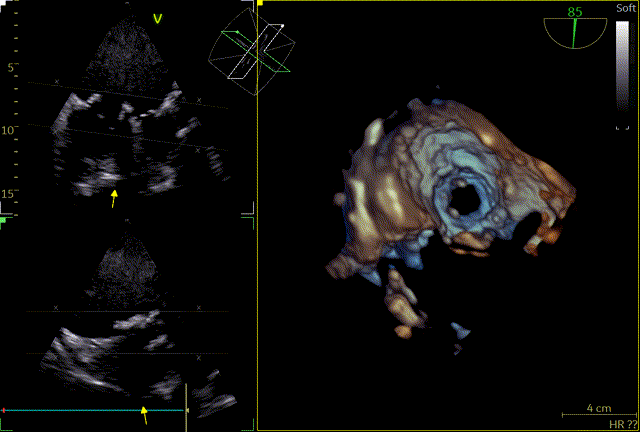

术后即时食道超声示:二尖瓣未见瓣周漏,生物瓣功能良好,三尖瓣未见明显返流。

术后床旁超声描述:MVR+TVP术后,双房增大。二尖瓣位为人工生物瓣回声,瓣环位置固定,瓣叶活动良好,未见赘生物回声。PHT法测二尖瓣人工生物瓣口面积:3.8cm²,三尖瓣见成形环强回声,CDFI:未见异常。